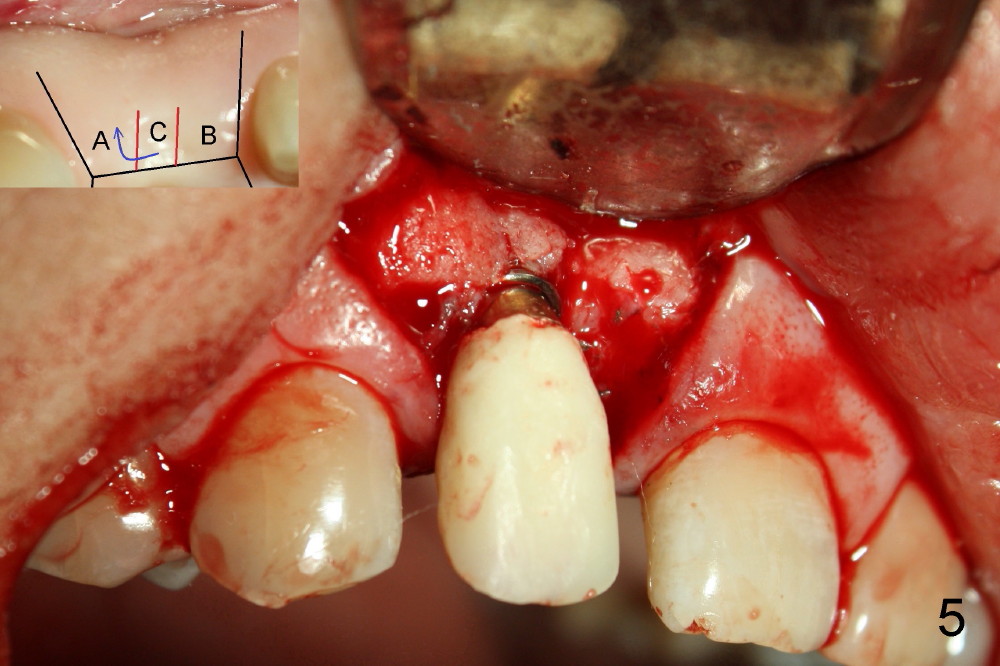

To increase buccal soft tissue bulk, the transverse incision is made lingual to the original socket (Fig.2 *). When the flaps are raised, the alveolar ridge appears to be deviated buccally; the implant (3.8x14 mm, insertion torque ~ 35 Ncm) also looks to be tilted too buccally even though it is placed in the middle of the ridge (Fig.3). An angled abutment (3.9 mm, 25º, 2 mm cuff, Torx A) has been adjusted buccally (Fig.4). The immediate provisional looks long (Fig.5). When the buccal flap is modified (Fig.5 insert) and sutured (Fig.6), the provisional looks to be tilted buccally. A custom Zirconium abutment should be used later on. All of these difficulties are due to delayed implantation with bone atrophy and are avoidable using immediate implant technique. Or check occlusion at the initial stage of osteotomy.